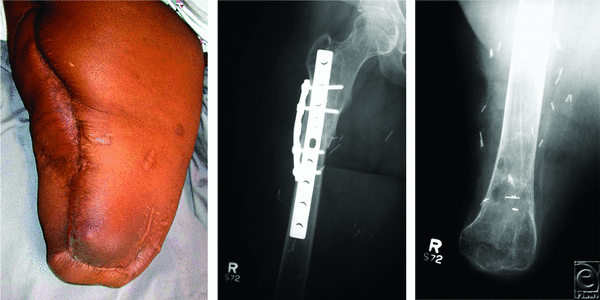

A lateral thigh incision for the recipient tibia was made through previous incisions, followed by an anterior midline longitudinal incision from the knee to the ankle. Medial and lateral fasciocutaneous flaps were elevated (Fig 2, left). The soleus and the gastrocnemius muscles were resected, and the fibula was excised. The anterior and lateral compartment muscles were carefully dissected off the tibia, leaving only the anterior tibial, posterior tibial, and peroneal arteries, and the surrounding soft tissues attached to the tibia. Distally, the dorsalis pedis, peroneal, and posterior tibial arteries and veins were dissected and ligated at the ankle. The foot was amputated at the tibiotalar joint, and the tibia was converted into a vascularized bone flap (Fig 2, middle). The popliteal artery and veins were dissected free at the distal thigh and the popliteal fossa.

The remnant distal femur was removed and disarticulated from the knee joint, which allowed the tibia to be rotated vertically. A soft tissue trough was created in the thigh, where the mid femur had been previously located. For proper length match, 10 cm of the distal tibia were removed. Osteosynthesis between the proximal femur and the distal tibia was achieved with an anterior internal 9-hole, 4.5-mm, narrow dynamic compression plate and a 5-hole, 4.5-mm, narrow dynamic compression plate (Synthes, West Chester, PA) placed 90° and lateral to the first plate (Fig 3, middle). The soft tissue defect was reconstructed with local muscle and tissue. Wounds were closed in multiple layers over 2 drains. The patient was discharged on postoperative day 11. She returned 2 months after surgery for an operative debridement of a small infected distal thigh seroma that grew Enterococcus faecalis. She was placed on intravenous and oral antibiotics.

At 3.5 years after surgery, she had an unstable wound at the distal lateral tibial condyle that prevented her wearing her prosthesis. She underwent resection of this wound and soft tissue coverage by a rhomboid fasciocutaneous flap (6 × 6 cm). The wounds healed without further complications (Fig 3).